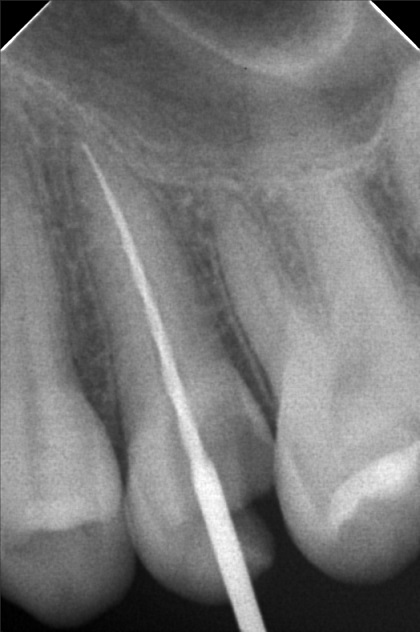

Edit Record Check our patient data records. Add patient information Patient Info Profile picture Last Name First Name Middle Name Birthdate Age Street Barangay City Country Zip Code Contact number Email Procedure 10/01/22 - OP(L); RESTO #26 ; #48; ACCESS #25 Scouting file #10 20mm; Closed with formocresol; Prescribed Tramadol +Paracetamol 325mg 10/08/22 - FILE 35 -19mm, CLOSED W/ CAMPHENOL; RESTO #22(LINGUAL), #47 (O & BUCCAL PIT) 10/15/22 - FILE 35 - 19mm, CLOSED W/ FORMECRESOL, RESTO #18(OB), #27, #28 10/22/22 - OBTURATE, FINAL RESTO#25, RESTO #16 (OL), #38 (O) File jamjam.jpg File 2 jamjam_02.jpg File 3 jamjam_03.jpg File 4 jamjam_04.jpg File 5 jamjam_05.jpg File 6 File 7 File 8 File 9 File 10 File 11 File 12 File 13 File 14 File 15 File 16 File 17 File 18 File 19 File 20 Retain Record Retain Record Yes No Save Your Changes